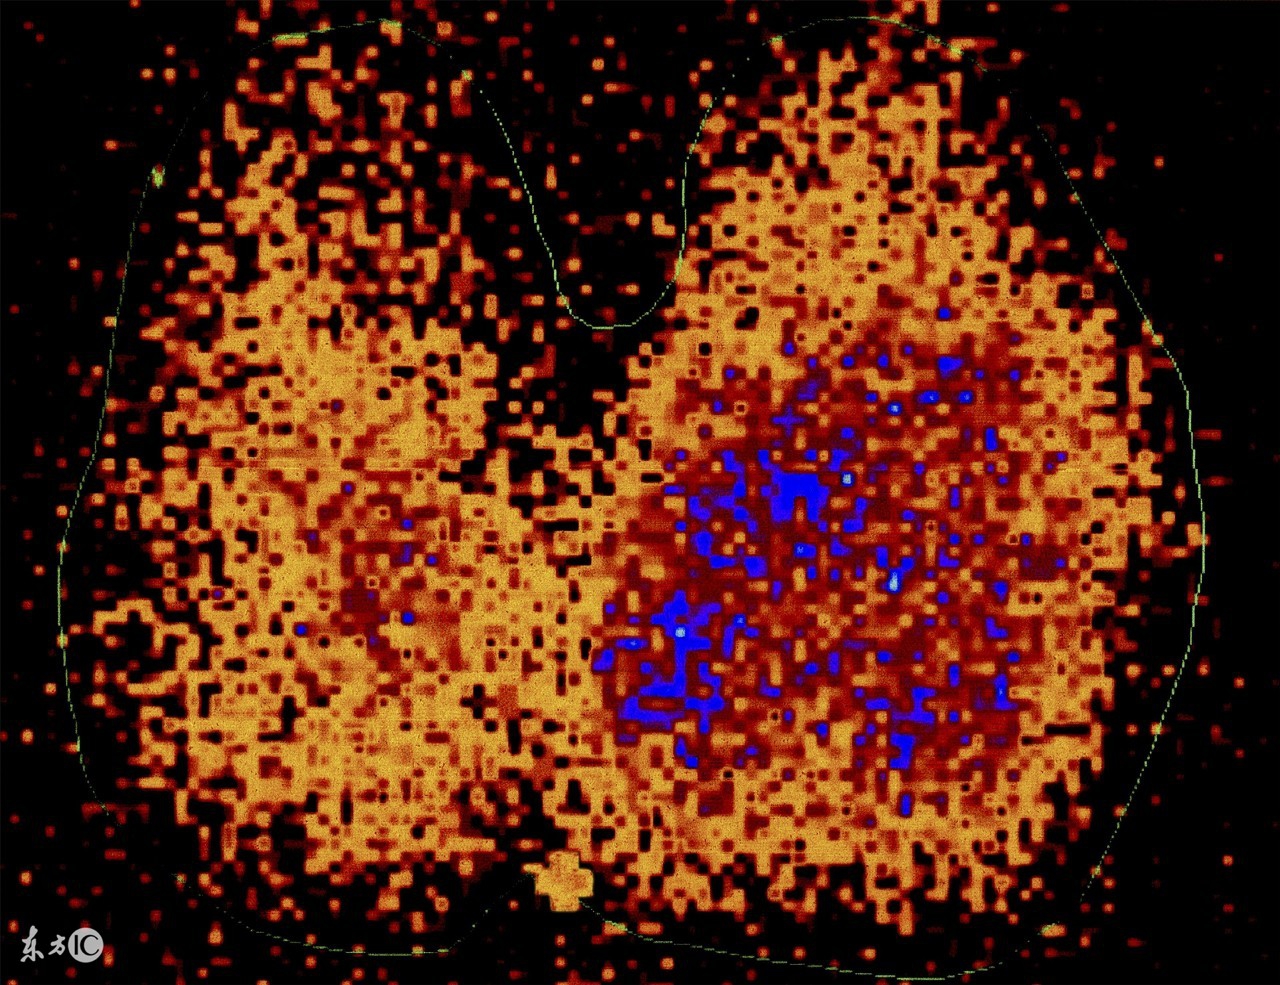

甲状腺同位素I131 (131i甲状腺功能测定不能吃什么)

甲状腺 I 131 试验膳食

甲状腺素131碘试验,甲状腺碘131试验视频